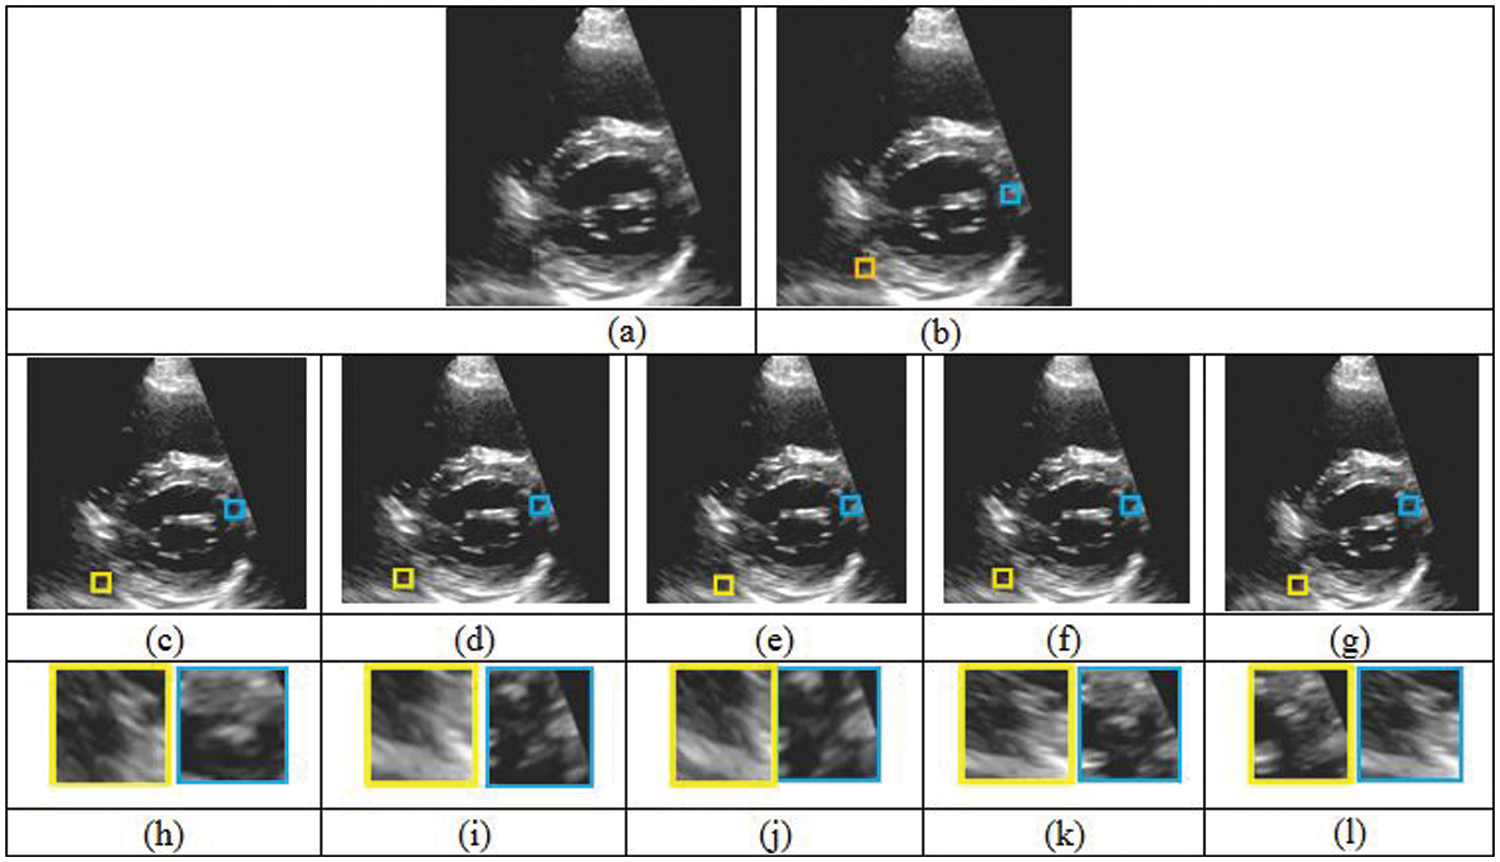

Figure 8: Comparison of five different reconstruction results. (a) Original cardiac ultrasound in PSAX view (b) ultrasound volume with missing regions. (c)–(g) Reconstruction results of FMM, MVR, NEWSON, Proposed Method I and II. (h)–(l) Magnified regions corresponding to the second row results

Figure 9: Comparison of five different reconstruction results. (a) Original cardiac ultrasound in A2C view (b) ultrasound volume with missing regions. (c)–(g) Reconstruction results of FMM, MVR, NEWSON, Proposed Method I and II. (h)–(l) Magnified regions corresponding to the second row results